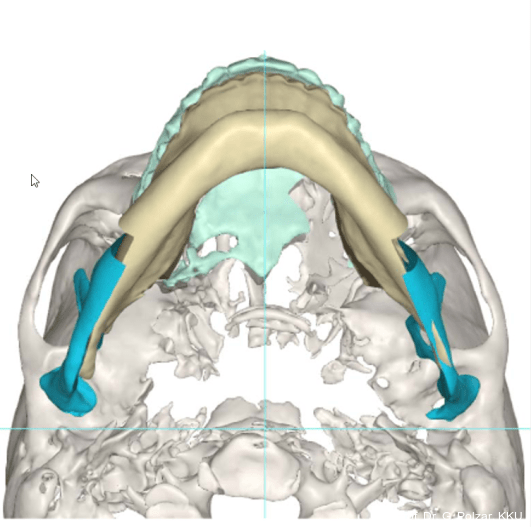

Die Operationsplanung erfolgte gemeinsam mit der Software von KLS-Martin (Abb. 12+13a–d).